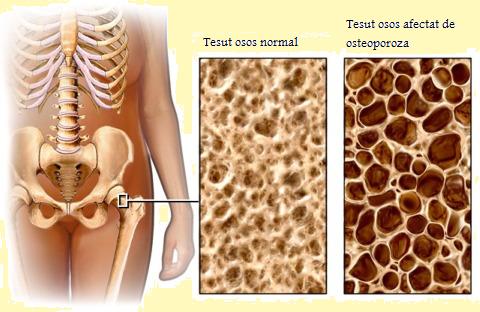

The bones of people suffering from osteoporosis are thin and very fragile. “Osteo” comes from the Greek “osteon”, which means “bone”, while “porosis” comes from the Greek word “poros”, meaning “hole, passage”. According to the medical dictionary Medilexicon, osteoporosis is a “Reduction in the quantity of bone or atrophy of skeletal tissue; an age-related disorder characterized by decreased bone mass and loss of normal skeletal microarchitecture, leading to increased susceptibility to fractures”.

German scientists have brought to light a molecular mechanism that adjusts the balance between bone formation and resorption. They were able to show that two different forms of a regulating gene – a short and a long isoform – determine this process. Osteoporosis is a disease that causes the fragility of the bones, leading to an increased risk of fractures (breaks or fissures) than in the case of healthy bones.

Osteoporosis occurs when the bones lose minerals, such as calcium, faster than it can replace it; this leads to a bone thickness decrease (the decrease of the bone mass or density). As a result, the bones become thinner and lose their density, so that the slightest impact or accident can lead to severe consequence fractures. They are also called minor trauma fractures or fragility fractures.